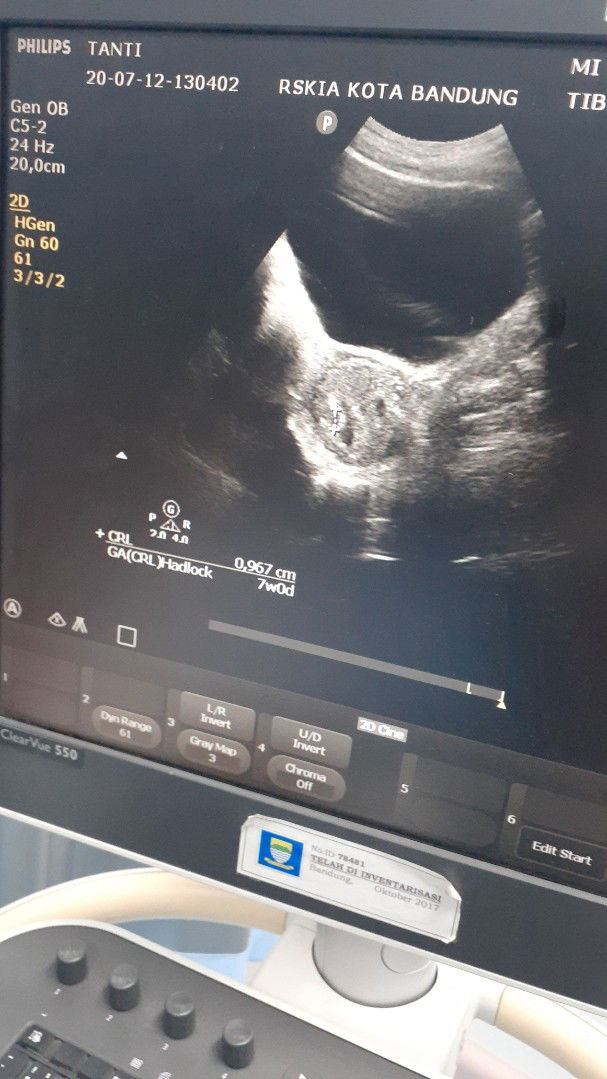

usg

Maaf bunda saya mau bertanya, barangkali disini bunda2 ada yang sama. Waktu saya usg minggu kemarin usia kandungan saya 7 minggu, tapi kata dokter masih keliatan kantung kehamilan nya aja, katanya sih karna kehamilan nya masih kecil, dan pertanyaan saya apa wajar ya usia kehamilan 7 minggu masih keliatan kantung kehamilan nya aja janin nya belum kelihatan ?

Wajar Bun ada janinnya nanti pas 10weeks-12wekss